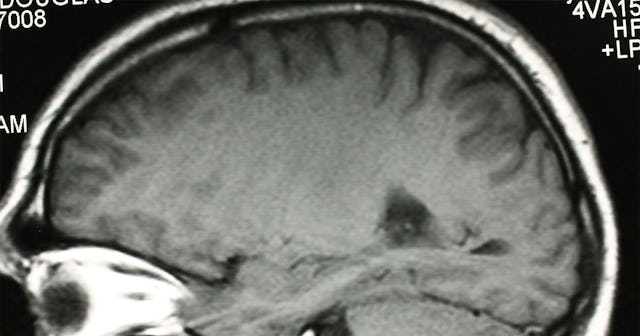

Two of the most common symptoms long haulers experience are fatigue and cognitive impairment, known more informally as “brain fog.” Researchers don’t know why some folks are experiencing these lingering effects, but a new theory is exploring the link between long COVID and brainstem dysfunction.

If that sounds scary or intimidating—it is. Brainstem dysfunction is related to chronic pain, migraine, and myalgic encephalomyelitis, also known as chronic fatigue syndrome (ME/CFS)—life altering diagnoses that are really devastatingly serious.

ACE2 receptors are found throughout your body—in your nose and throat, but also in your heart, your digestive tract, and in your brainstem, “which has a relatively high expression of ACE2 receptor compared with other brain regions.”

While it’s still unclear whether COVID long haul symptoms are a result of the virus invading the brain or a result of inflammation due to your body’s large-scale immune response to the virus, researchers have found preliminary evidence that COVID-19 is neuro-invasive. Meaning: the virus itself is invading the brain and the nerves near the brain.

Researchers have noted that functions of the brain stem—including those responsible for maintaining cardiovascular, gastrointestinal, and neurological processes—correspond with symptoms of long haul COVID in many ways.